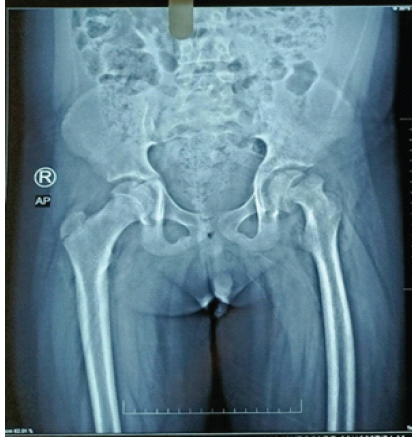

Hip disorders in the paediatric population (patients <16 years) represent a varied collection of conditions ranging from traumatic, developmental, infectious, neoplastic, and metabolic causes [1]. These pathologies, if not promptly diagnosed and treated, frequently result in long-term morbidity, including permanent deformities, chronic pain, gait abnormalities, and compromised quality of life in adulthood [1,2]. The unique developmental anatomy of the pediatric hip, characterized by the presence of a vulnerable physeal plate and changing vascular patterns, contributes to its susceptibility to specific age-related diseases [3]. Common non-traumatic paediatric hip disorders include developmental dysplasia of the hip (DDH) (Fig. 1), Legg-Calvé-Perthes disease (Perthes’) (Fig. 2 and 3), slipped capital femoral epiphysis (SCFE) (Fig. 4), and infective conditions such as septic arthritis (Fig. 5) and tubercular arthritis [3].

Figure 4: Left slipped capital femoral epiphysis.